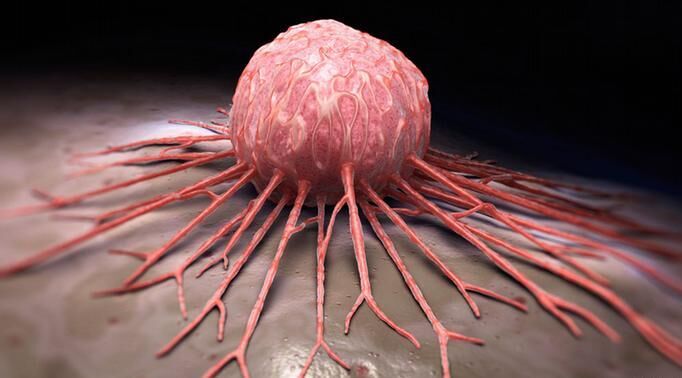

به گزارش سایت طلا ، ميوهها و سبزی ها به علت داشتن ويتامينها، مواد معدنی، آنتی اكسيدانها و فيبر نقش مهمی در پيشگيری و درمان انواع سرطانها، بيماری های قلبی - عروقی، سكته مغزی، پوكی استخوان، ديابت و چاقی دارند.

برای پیشگیری از سرطان

اسفناج، جعفری، توت فرنگی